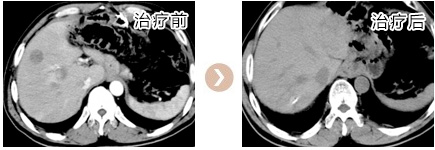

患者林##,男性,48岁,以2008.07.10于我院行“根治性全胃切除术”,病理分期:PT4N3M0,术后一个月复查CT:肝内多发占位,考虑转移癌。先后予化疗、肝动脉灌注化疗及栓塞、肝脏转移瘤射频消融、粒子植入及再次手术等综合治疗;2014.07.22复查胸部CT示右肺下叶和左肺上叶转移,化疗和肺结节粒子植入等综合治疗。现已无瘤存活8年,2016.6.19门诊随访,一般情况良好,生活质量高。

患者林##,男性,48岁,以2008.07.10于我院行“根治性全胃切除术”,病理分期:PT4N3M0,术后一个月复查CT:肝内多发占位,考虑转移癌。先后予化疗、肝动脉灌注化疗及栓塞、肝脏转移瘤射频消...